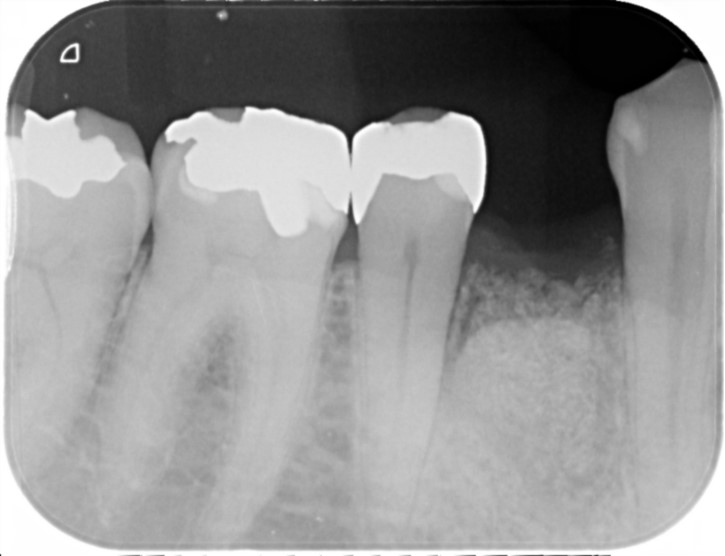

40代 女性

左上5番が歯根破折を起こし保存不可能な状態でした。

抜歯して3か月経過し骨の状態も問題のないことをCTで確認を行いました。

手術から3か月後に無事に被せ物まではいりました。かみ合わせも問題なく調子よく経過し現在術後2年経過しておりますが問題ありません。

左上の青い線で囲んであるとことが新しい歯になります。

経過も問題なくなんでも噛むことができるようになりました。

費用 | 45万円 |

治療期間 | 6か月 |